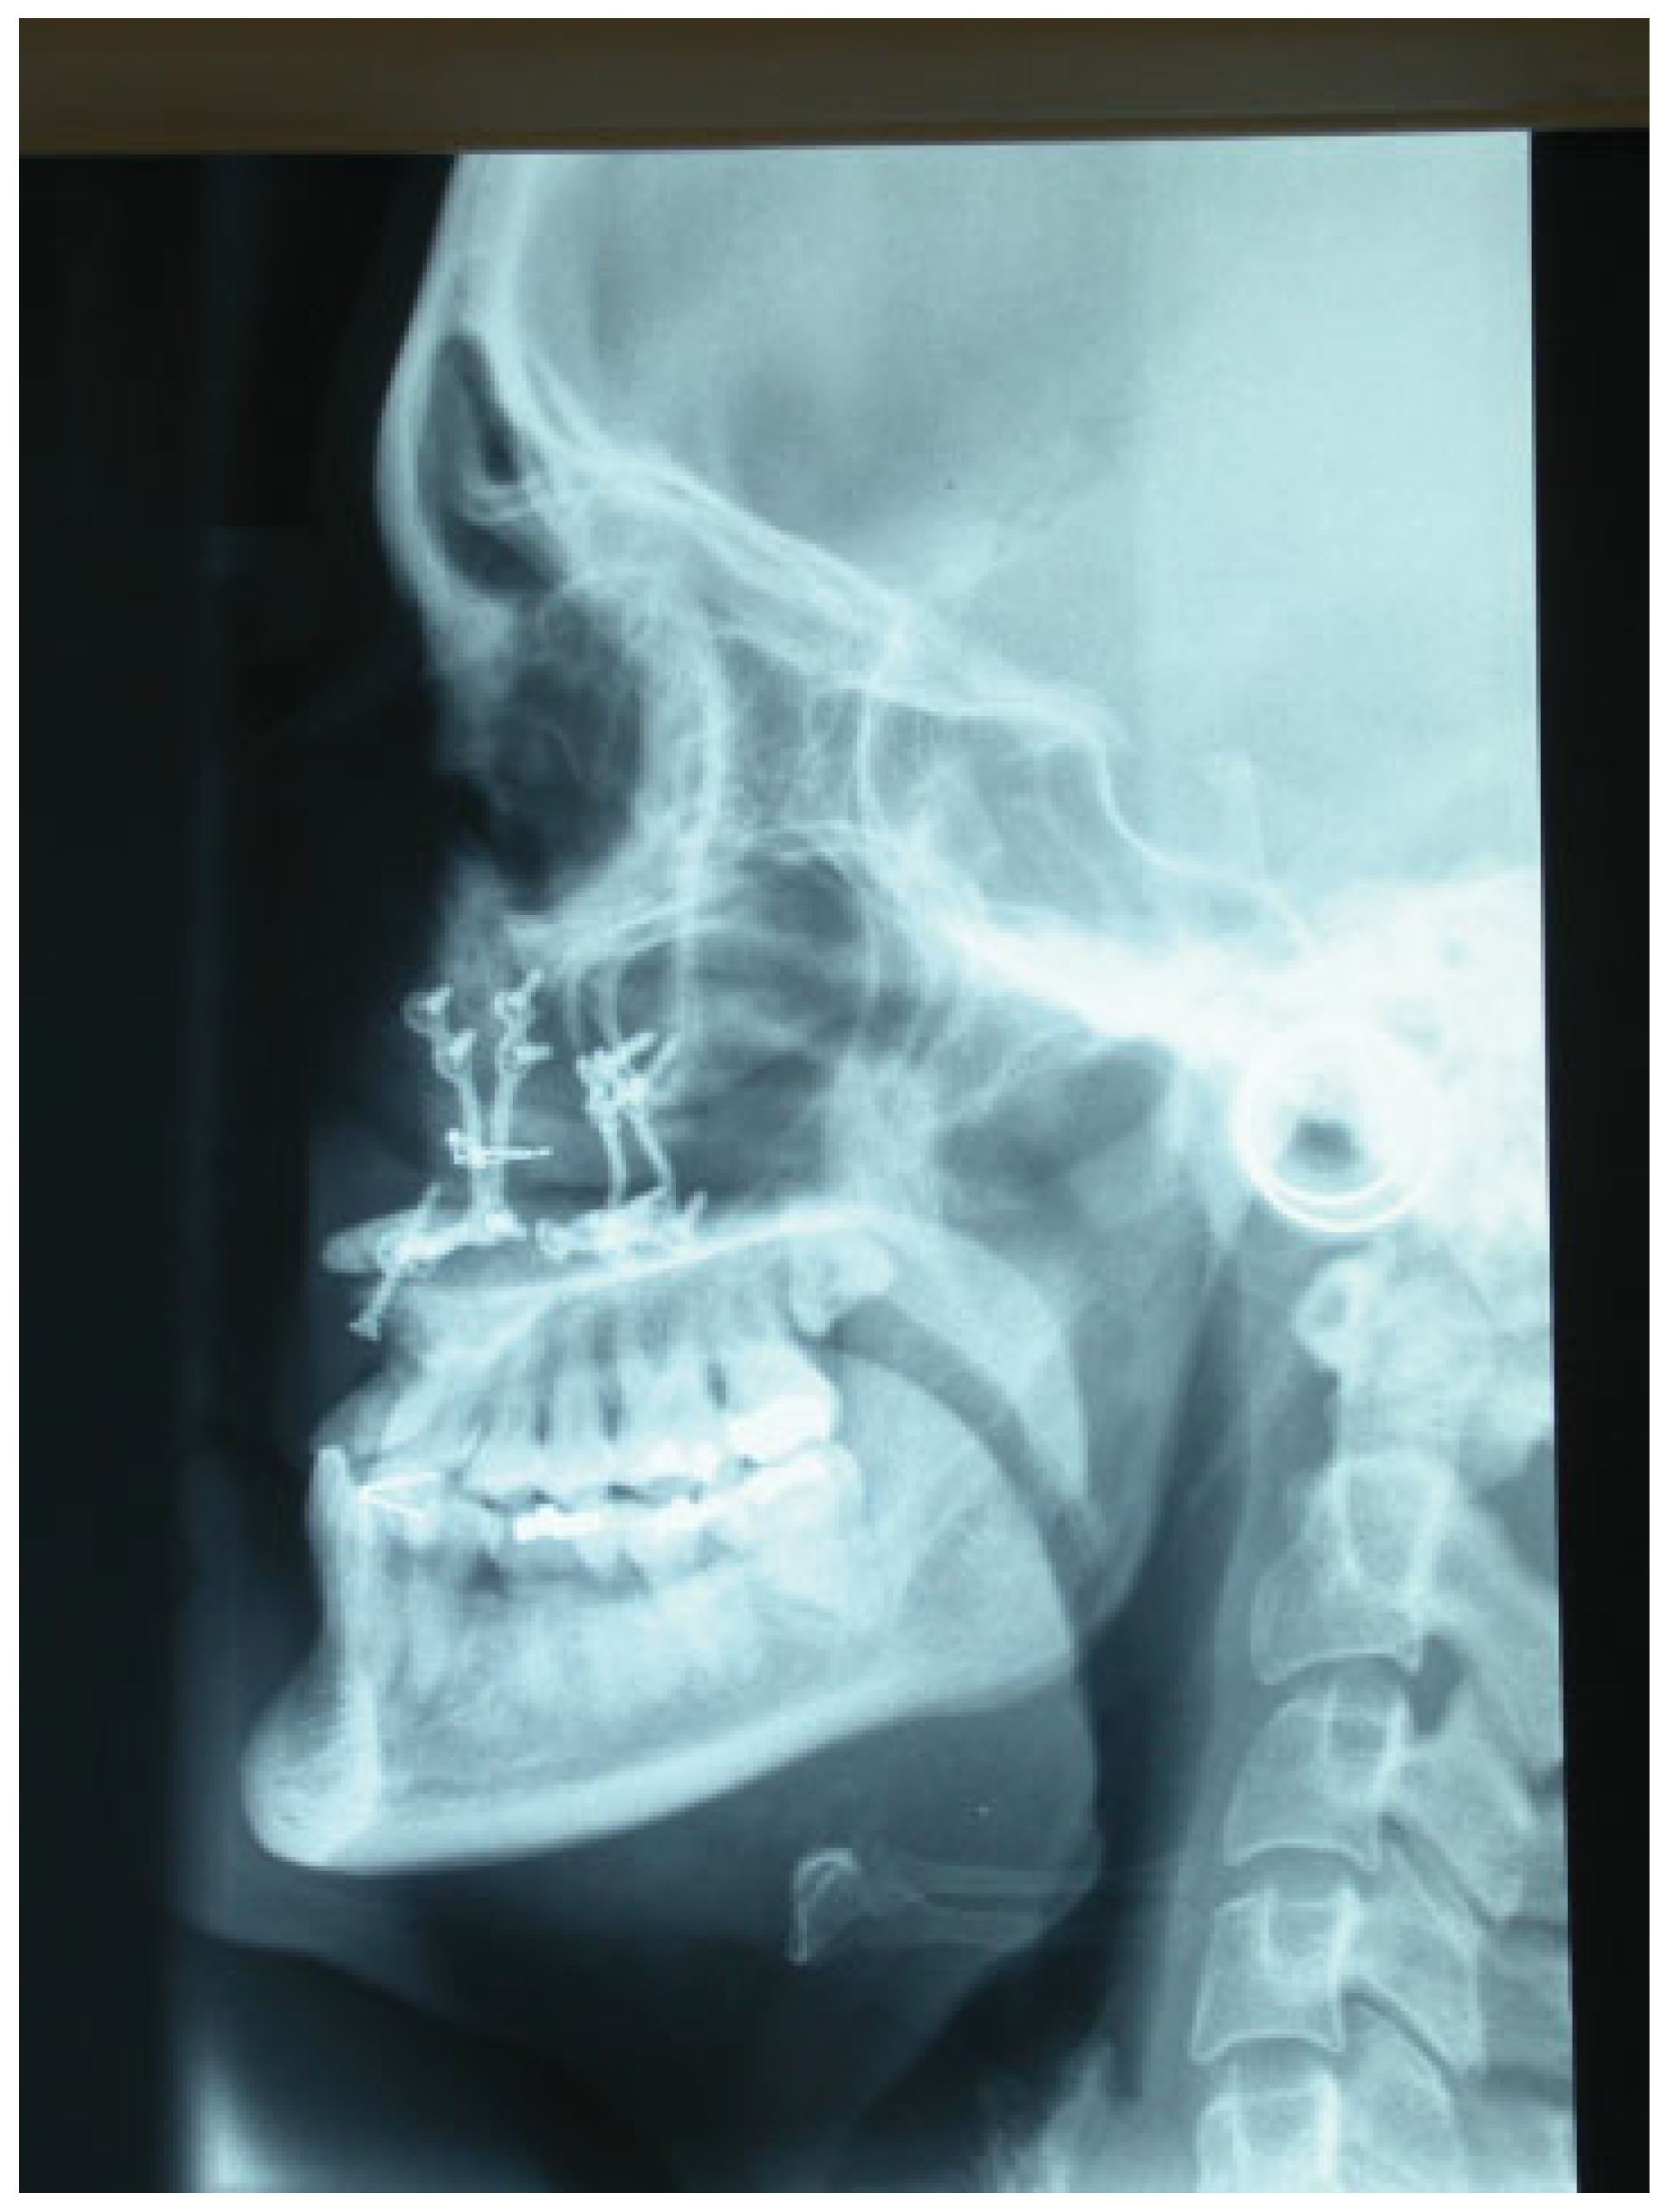

Figure 3.

Impaction and fixation of the Le Fort I osteotomy as a conventional procedure. Screw the plates to the fixed maxillary fragment.

Figure 4.

Figure drawing in sagital view. Screw the plates to the fixed maxillary fragment and fixation of the bone block with a wire.

Tele-lateral radiograph. The grafts are fixed with stainless steel wires and the maxillary fixation is performed with titanium miniplates.